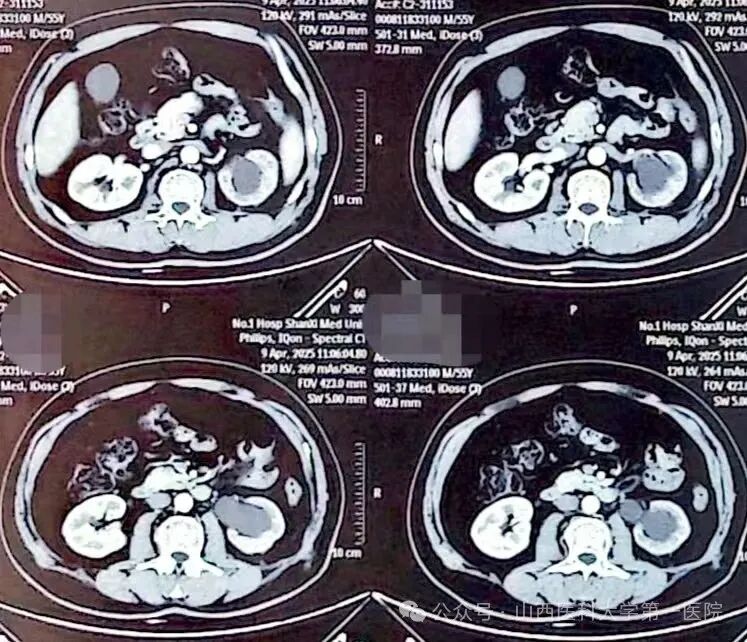

55岁男性患者,2024年3月因“左侧输尿管结石”在外院行输尿管镜碎石术;2024年9月在外院诊断为“左侧输尿管上段狭窄”,狭窄段长约3cm,行“开放左侧输尿管成形术”,术后半年拔除输尿管支架管,复查显示肾积水无改善;2025年4月,为求进一步诊治就诊于山医大一院,经影像学检查明确诊断为“左侧输尿管上段狭窄”,此次狭窄段长约1cm,位于既往手术区域。

术前CT